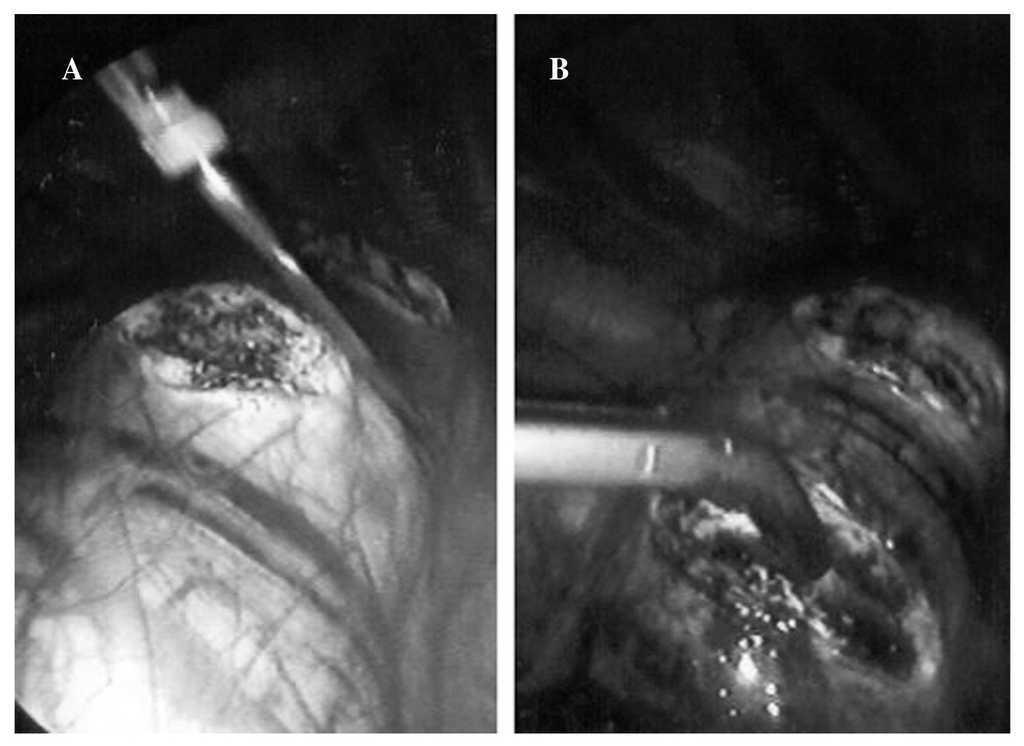

Todos los pacientes fueron intubados de forma selectiva con un tubo orotraqueal de doble luz para obtener el colapso pulmonar. A continuación se les colocó en decúbito lateral y con 45º de rotación hacia prono, con la convexidad de la curva hacia arriba y un rodillo bajo la axila declive. En los casos de cifosis se situó el lado derecho arriba. La rotación hacia prono del paciente permite que el pulmón caiga hacia la parte anterior del tórax, lo cual facilita el acceso a la columna vertebral. Los paños quirúrgicos se dispusieron de forma estándar para una toracotomía posterolateral y en todos los casos estuvo disponible una caja de instrumental para efectuar una toracotomía de emergencia. El abordaje se realizó a través de 3 puertas de entrada de 12 mm de diámetro, la primera situada en el sexto o séptimo espacio intercostal, en la línea axilar media, para permitir una óptima exploración del hemitórax y decidir la disposición de las 2 puertas restantes, por lo general en situación yuxtadiafragmática la segunda y anterior a nivel del ápex de la curva la tercera para completar la triangulación. A continuación se procedió a la apertura de la pleura, incisión del anillo fibroso mediante electrocauterio y resección de los discos y platillos vertebrales (fig. 1), así como a la liberación parcial del ligamento longitudinal común anterior. Esta liberación anterior fue más amplia en los casos de cifosis. La correcta localización de los discos que debían extraerse se comprobó con un intensificador de imagen de rayos X en todos los casos.

Fig. 1. Imágenes endoscópicas: apertura de la pleura mediante electrocauterio (A) y resección de disco intervertebral mediante discotomo (B).